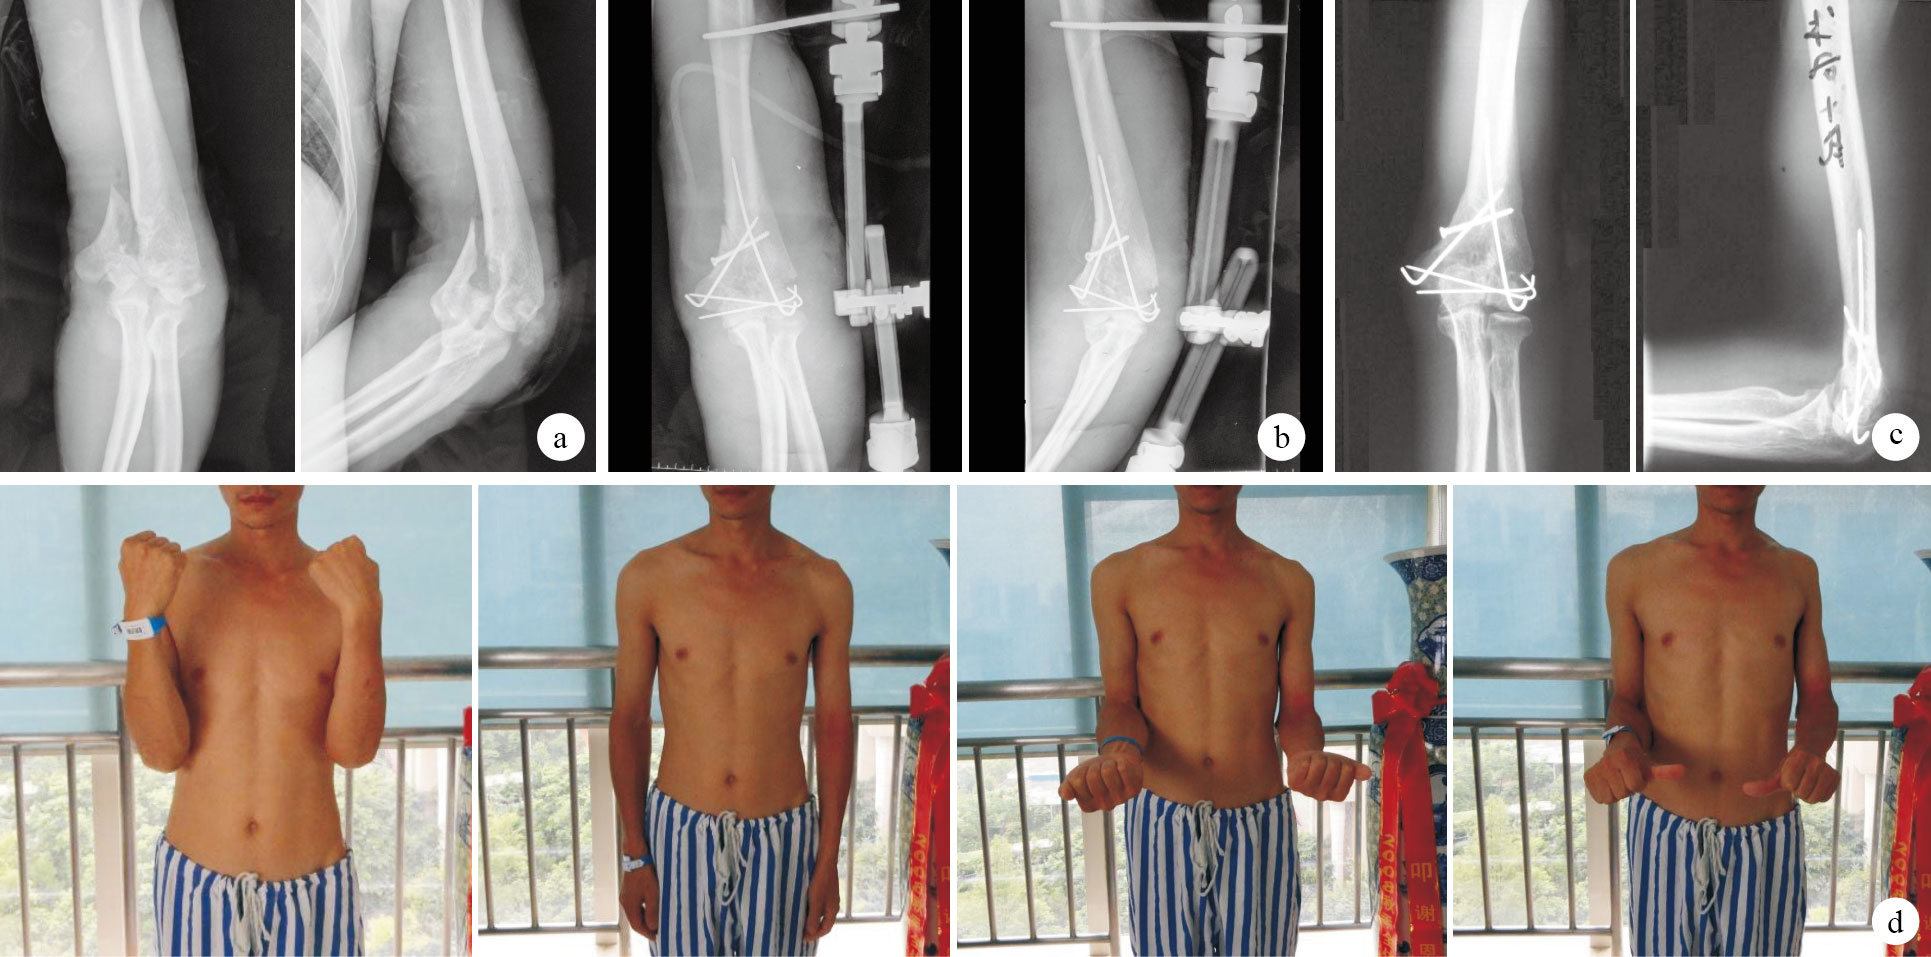

術后發生針道反應3例,切口感染1例,均經換藥抗感染等對癥治療愈合;其余患者切口均Ⅰ期愈合。36例患者獲隨訪,隨訪時間9~48個月,平均25.4個月。9例神經損傷者中8例恢復,1例尺神經損傷未恢復。術后2、3、5個月分別發生1例異位骨化,骨折愈合后行松解手術,未再次出現異位骨化。1例患者因術后發生感染形成慢性骨髓炎,控制感染后于術后9個月再次手術更換內固定后骨折愈合;其余患者骨折均順利愈合,愈合時間6~14個月,平均9個月。1例患者術后12個月出現遲發性尺神經炎,行尺神經松解前移術后神經功能恢復正常。隨訪期間所有患者均未出現骨缺血性壞死,無肘關節不穩及內固定物松動、斷裂等并發癥發生。末次隨訪時肘關節活動度:屈70~130°,平均105.0°;伸- 40~0°,平均- 25.0°;旋前40~90°,平均69.2°;旋后30~90°,平均75.6°。按Mayo肘關節功能評分(MEPS)和上肢功能評分(DASH)評價肘關節功能,獲優22例,良8例,中4例,差2例,優良率83.3%;按Cassebaum肘關節功能評分[2],獲優21例,良7例,可5例,差3例,優良率77.8%。見圖 1。